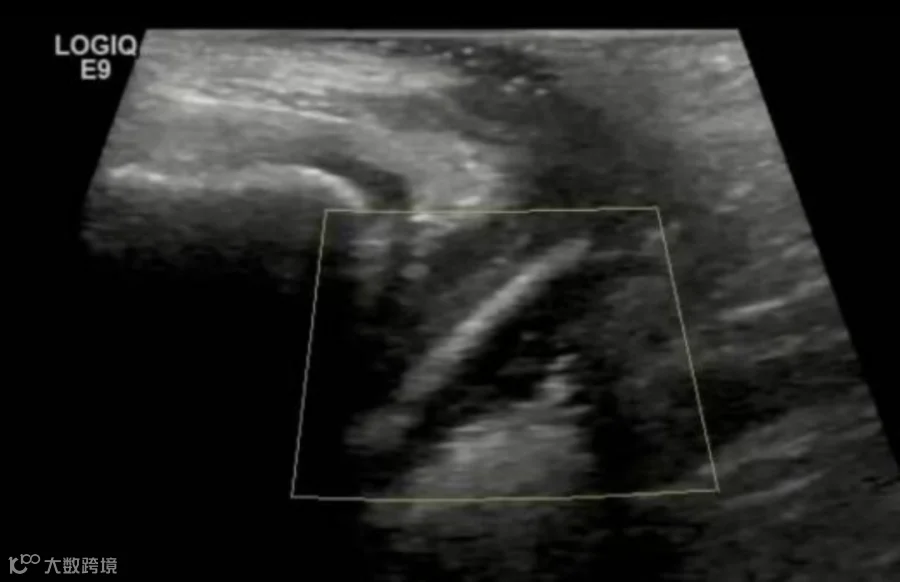

这名少年患者因青春期好奇心驱使,自行将52颗直径约5毫米的珠子经尿道塞入膀胱。4天后,出现了排尿困难、下腹疼痛等症状,在家人的陪同下前往医院就诊。

CT影像显示,这些珠子全部沉淀在膀胱最下端,不仅造成尿路梗阻,更可能因持续压迫导致膀胱黏膜损伤。